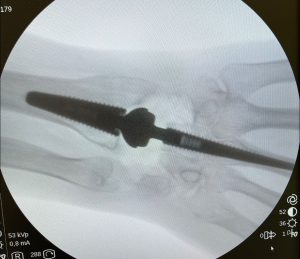

PATOLOGIAS MUÑECA - PRÓTESIS ARTICULARES Figura 4 - Artrodesis de articulación interfalángica proximal

Figura 4 - Artrodesis de articulación interfalángica proximal.